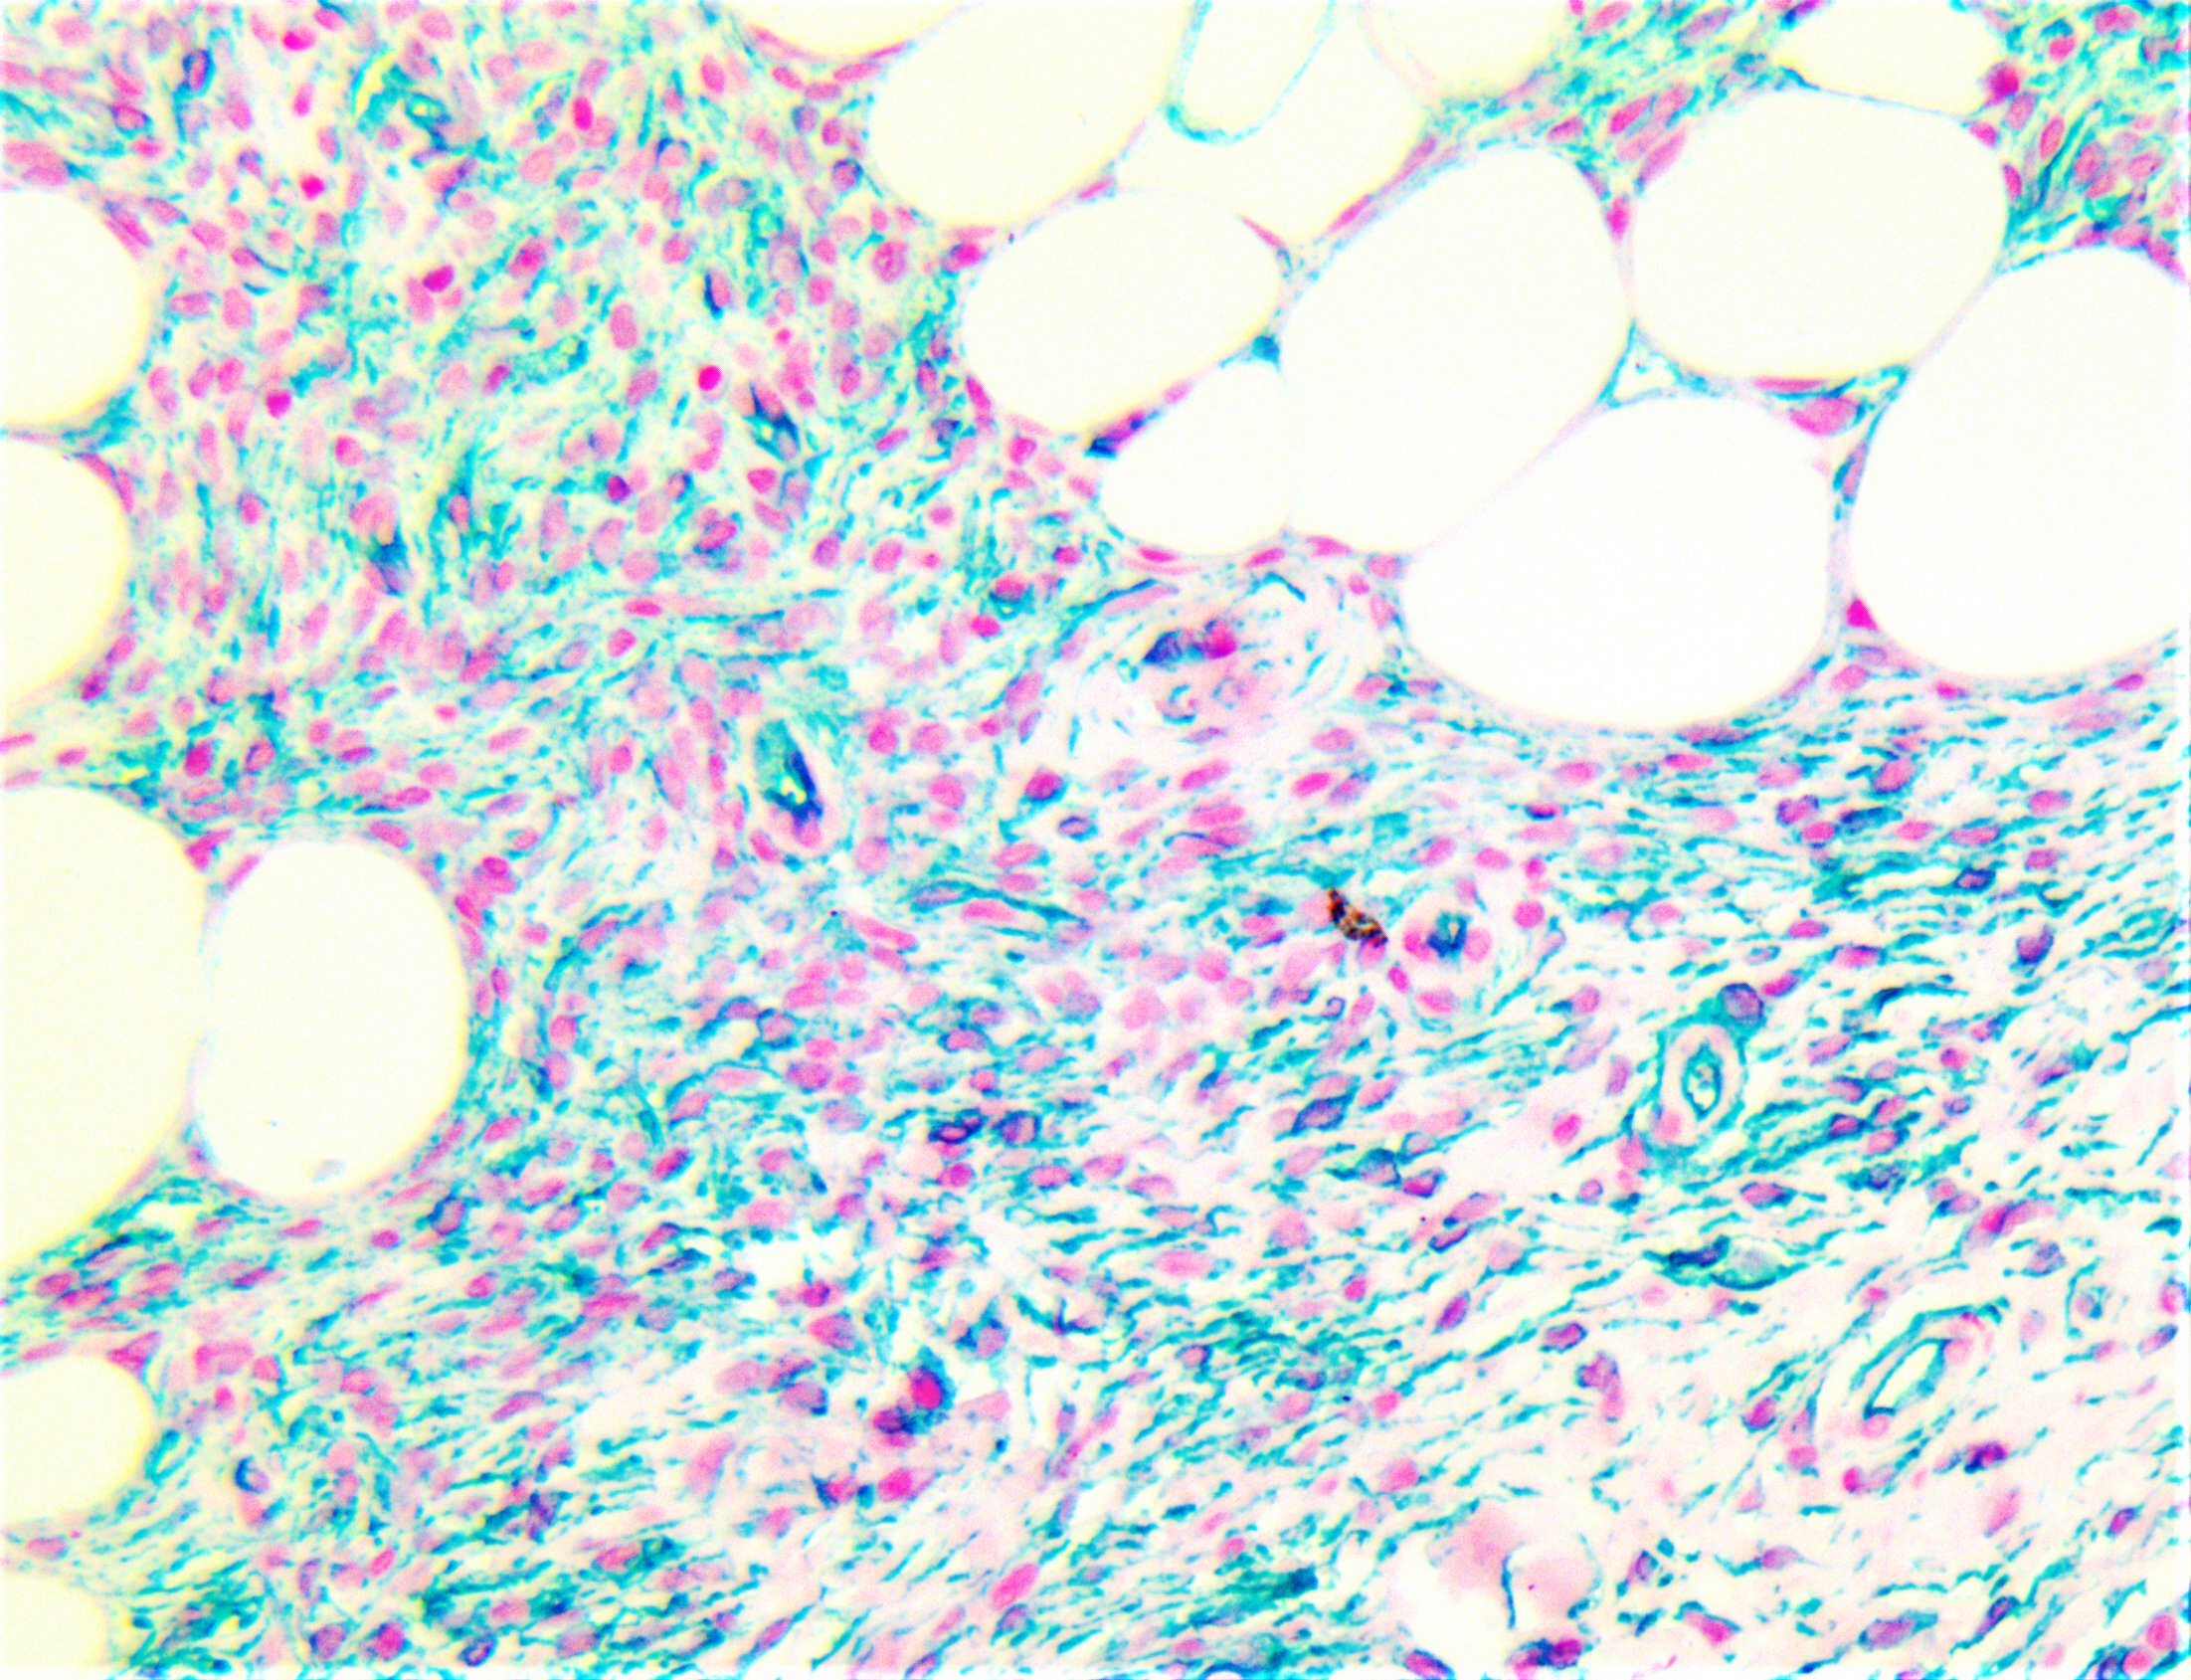

TintoFast CD34 functions as a cell-cell adhesion factor and cell-surface glycoprotein. It may also mediate the attachment of stem cells to bone marrow extracellular matrixes or directly to stromal cells. Cells expressing CD34 are normally found in the umbilical cord and bone marrow as hematopoietic cells, and in vascular endothelium. In addition to stem cell recognition, CD34 is expressed by vascular endothelium; it appears that proliferating endothelial cells express this molecule in greater amounts than resting cells. In comparison to factor VIII R Antigen, CD34 stains are stronger and appear to be more sensitive in nature. In tumors, CD34 is found in Alveolar Soft Part Sarcoma, pre B-ALL (positive in 75%), AML(40%), AMLM7 (most), Dermatofibrosarcoma Protuberans, Gastrointestinal Stromal Tumors, Giant Cell Fibroblastoma, Granulocytic Sarcoma, Kaposi’s Sarcoma, Liposarcoma, Malignant Fibrous Histiocytoma, Malignant Peripheral Nerve Sheath tumors, Meningeal Hemangiopericytomas, Meningiomas, Neurofibromas, Schwannomas, and Papillary Thyroid Carcinoma. A negative CD34 may exclude Ewing’s Sarcoma/PNET, Myofibrosarcoma of the breast, and Inflammatory Myofibroblastic tumors of the stomach. |

| Localization | Cytoplasmic, Membranous | Control | Trichoepithelioma, Desmoplastic Trichilemmoma, Dermatofibrosarcoma Protuberans, Kaposi’s Sarcoma | |